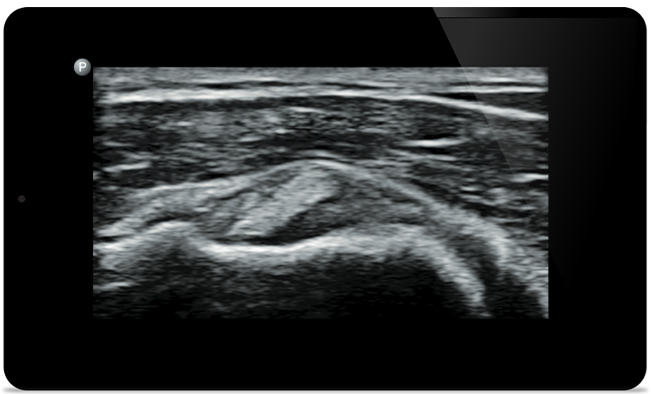

Lumify helps you see the fine details in muscles, joints, ligaments, tendons and cartilage to make a more accurate diagnosis of injuries.

Lumify can help you assess patients from head to toe, whether it’s plantar fasciitis, tendonitis or bursitis in the patellar tendon, or even shoulder instability in the rotator cuff.

Supraspinatus tendon tear